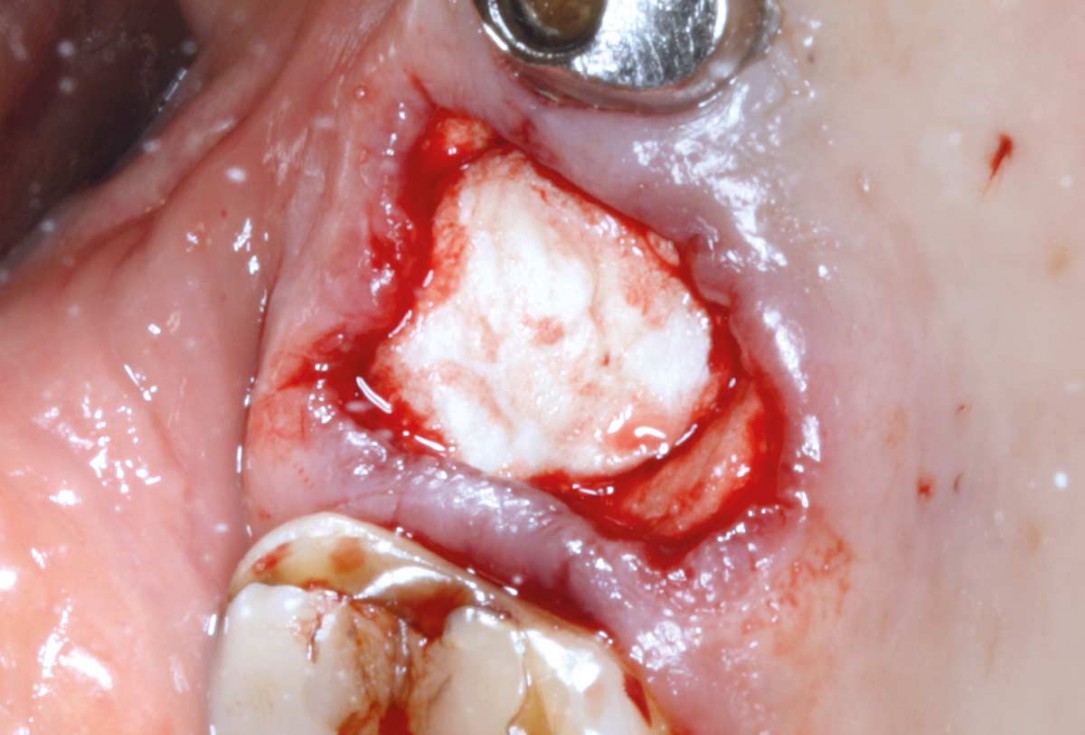

03/07 - Extraction socket filled with collacone®.Socket preservation with permamem® - Dr. M. Turco